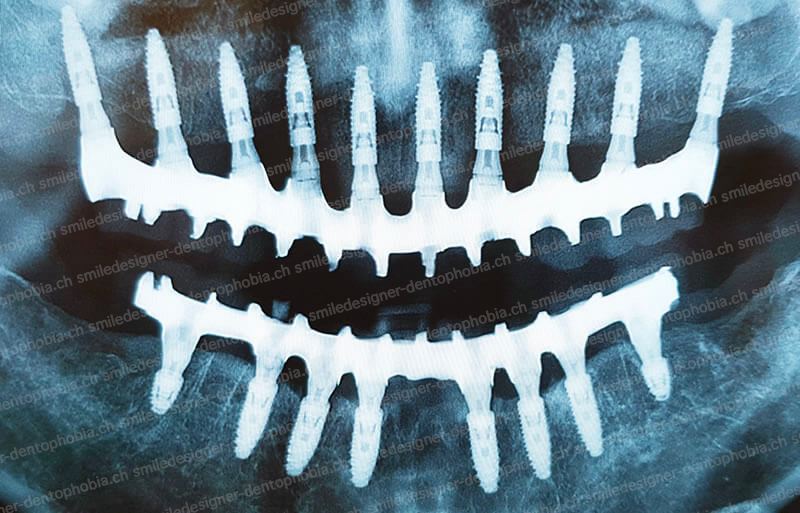

Cas clinique « DOMINO SURGERIES MCI » : Bridge implanto-porté sans extension postérieure (ALL ON 10/8). Version définitive des bridges avec un cosmétique en céramique. Double comblements de sinus et double greffes osseuses d’apposition pour la reconstruction du maxillaire.

Cas clinique « DOMINO SURGERIES MCI » : Bridge implanto-porté sans extension postérieure (ALL ON 8/6). Version définitive des bridges avec un cosmétique en céramique. Double comblements de sinus et double greffes osseuses d’apposition pour la reconstruction du maxillaire.

Version définitive des bridges avec un cosmétique en céramique (ALL ON 10/6). Double comblements de sinus et double greffes osseuses d’apposition pour la reconstruction du maxillaire.

- Première étape : pose de 6 implants au maxillaire et 6 à 8 implants à la mandibule dans la zone antérieure, pour restaurer immédiatement l’esthétique du sourire.

- Résultat final : une arcade dentaire complète, de molaire à molaire, avec des bridges en céramique, pour une mastication optimale et un sourire naturel.